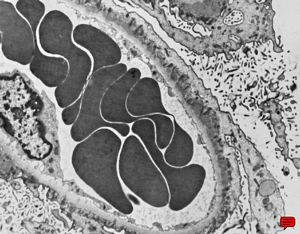

M,17y. | Alport syndrome - split and laminated basement membranes